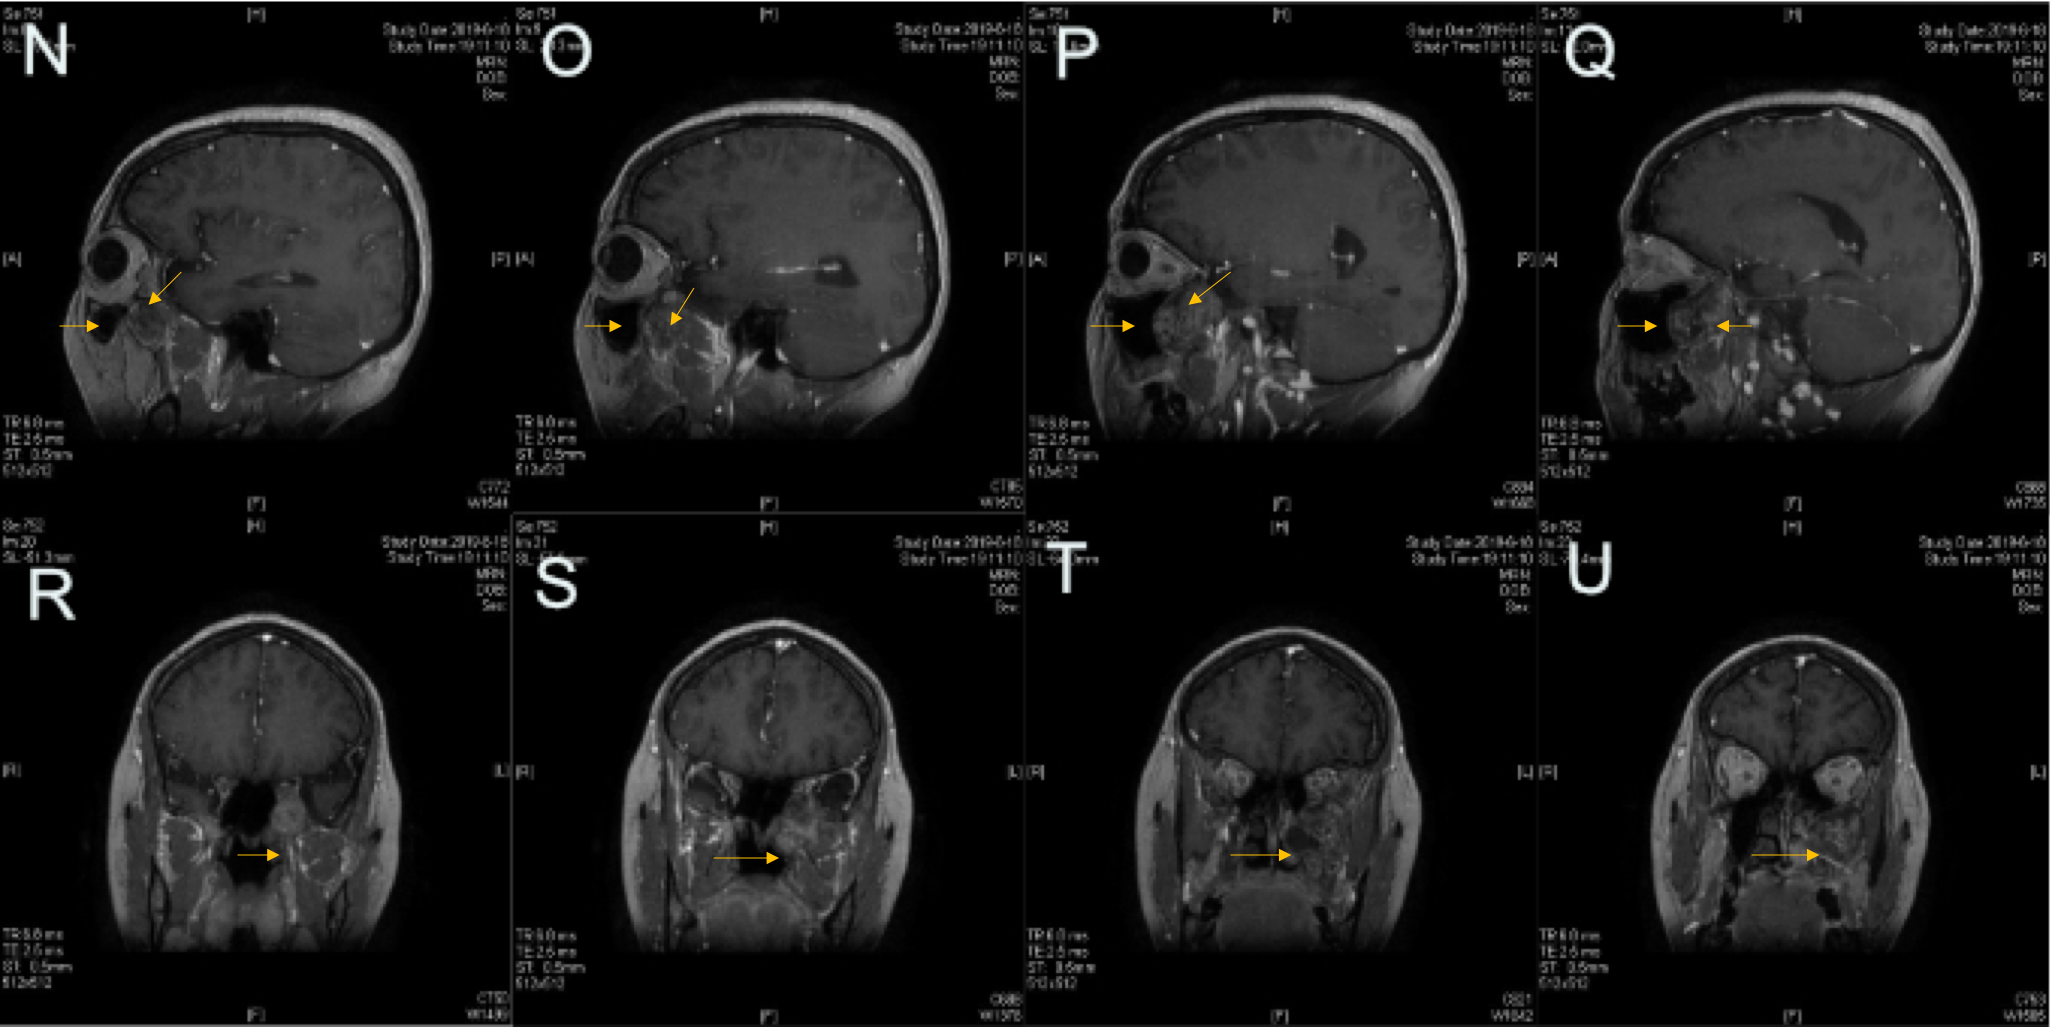

图2.PPF内肿瘤侵犯上颌窦后壁以及颞下窝,部分肿瘤向中颅底侵犯。

图3.诊断:左侧PPF肿瘤(术后病理:神经鞘瘤)